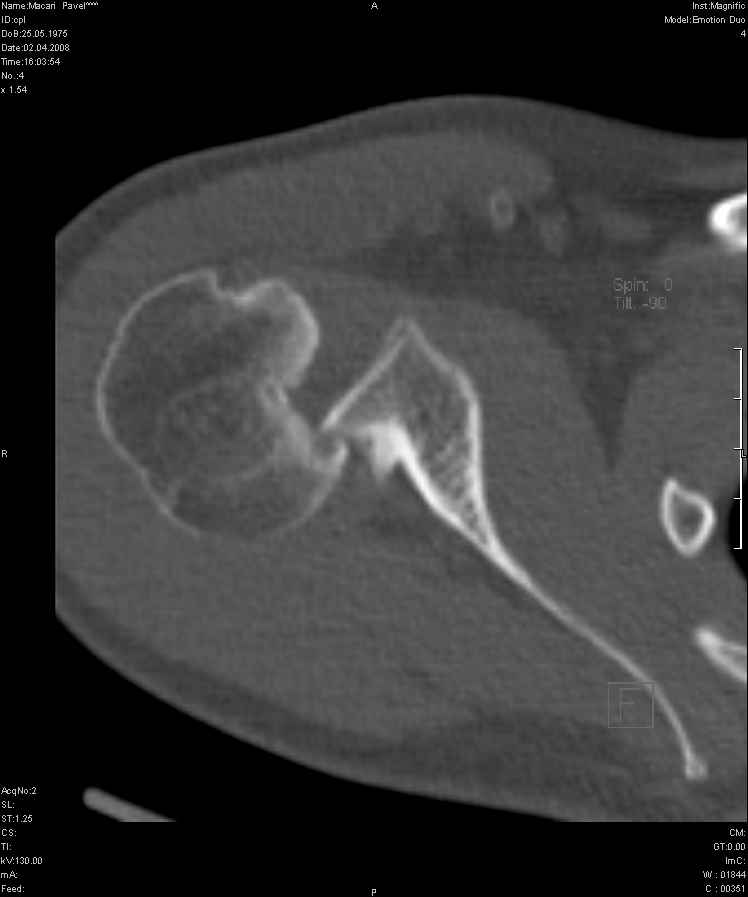

Задний вывих плеча действительно есть. Такой вариант вывиха по прямой рентгенограмме действительно не бросается в глаза. Травматологи-ортопеды в Молдавии есть.

Добрый день! А перелом Хилла-Сакса? Вывих-то можно вправить по Илизарову, а вот вывих+перелом? Какова перспектива?

Точен ли диагноз? Неодходимо ли оперативное вмешательство? Это очень важно для меня, поскольку я из Молдавии, а у нас специализированных учреждений нет. Даже предположительный диагноз поставили спустя год после травмы, направив на томографию (по обычным рентгеновским снимкам определить ситуацию не могли).